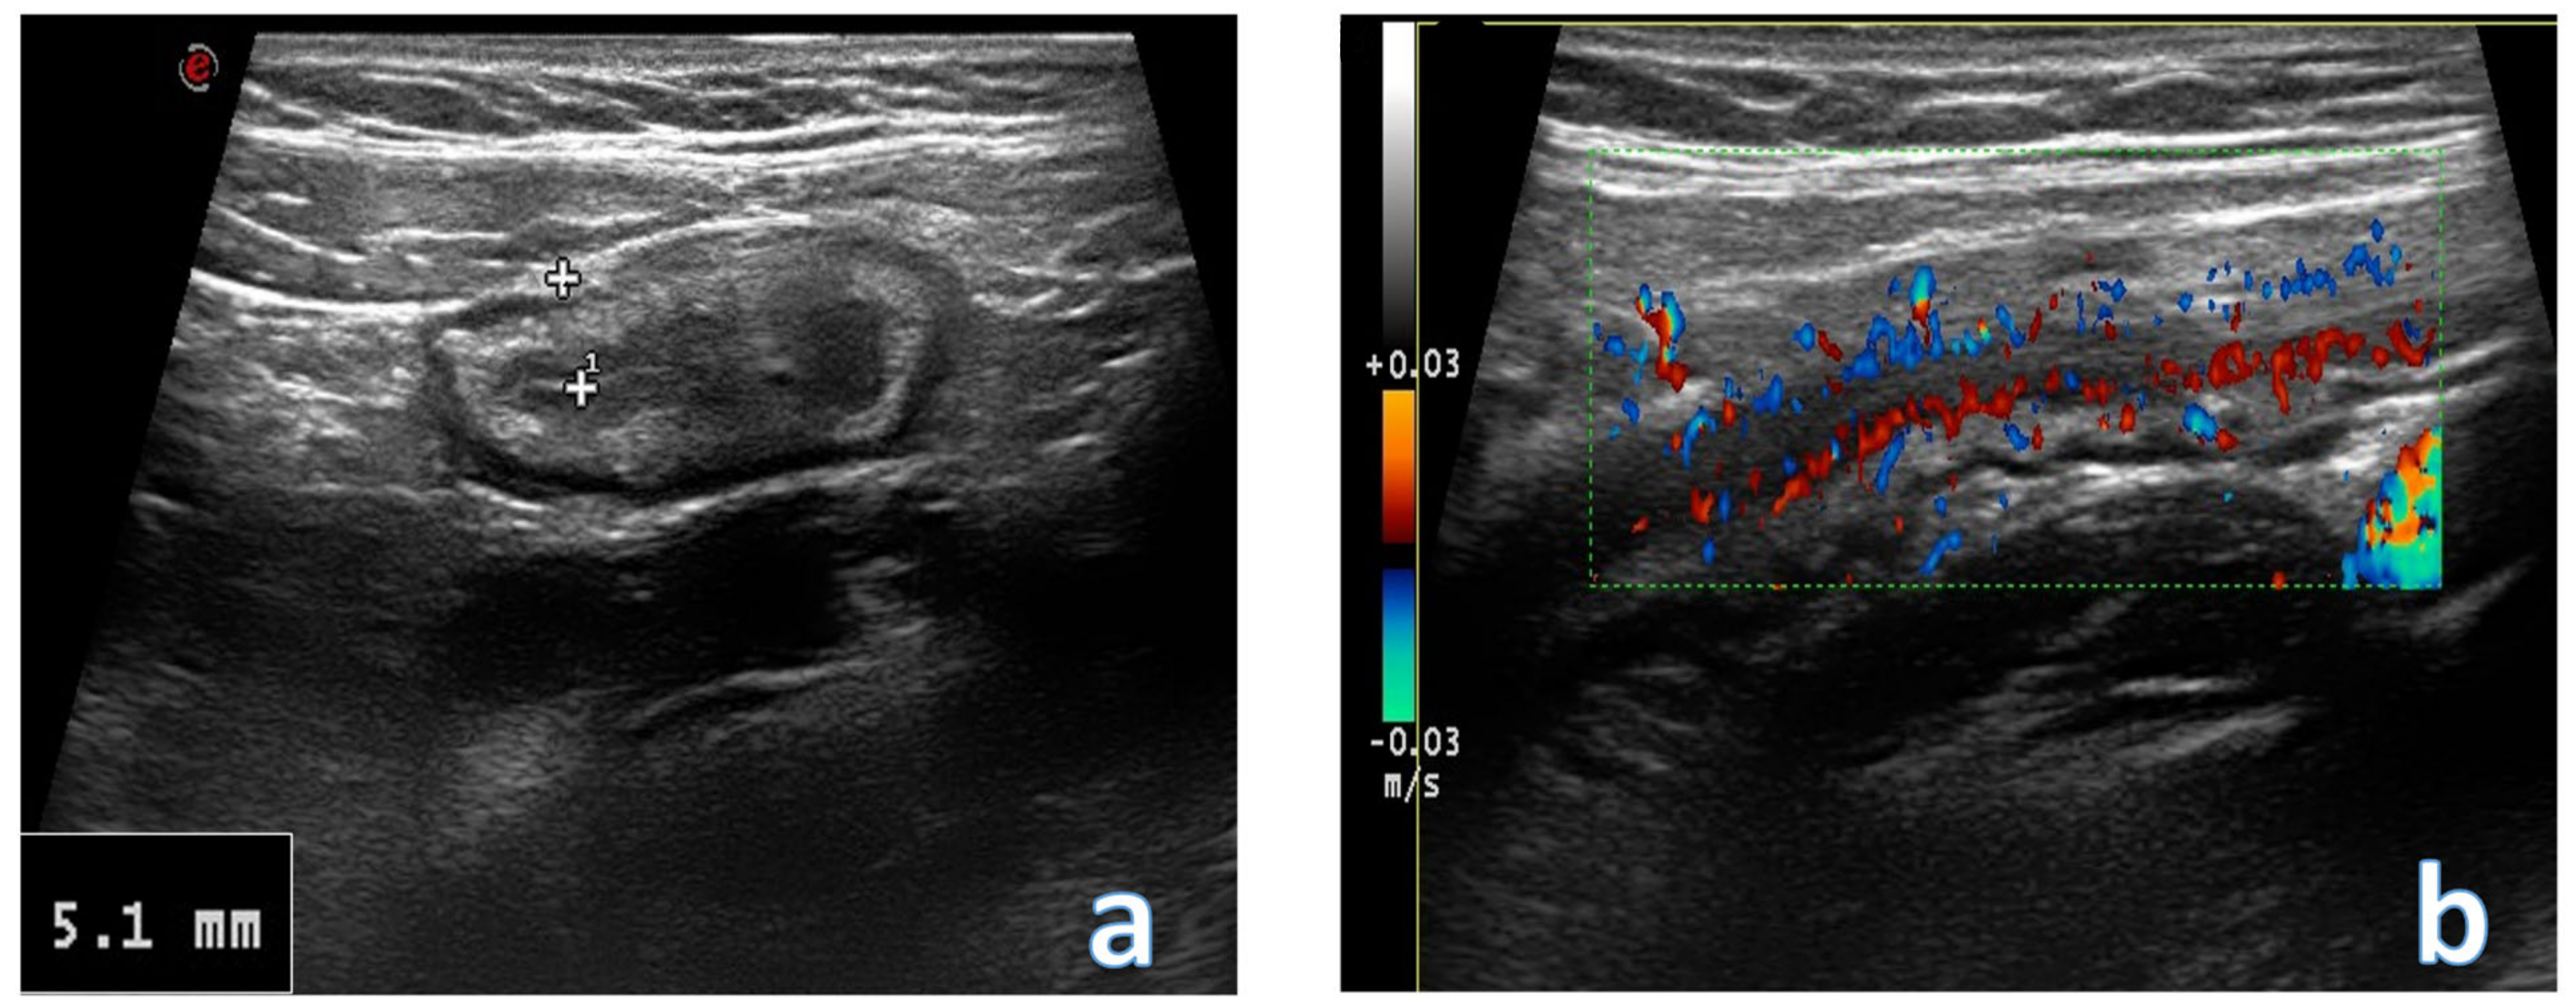

4. Acute Appendicitis

- Xu, Y.; Jeffrey, R.B.; Shin, L.K.; DiMaio, M.A.; Olcott, E.W. Color Doppler Imaging of the Appendix: Criteria to Improve Specificity for Appendicitis in the Borderline-Size Appendix. J. Ultrasound Med. 2016, 35, 2129–2138. [Google Scholar] [CrossRef]

- Summa, M.; Perrone, F.; Priora, F.; Testa, S.; Quarati, R.; Spinoglio, G. Integrated clinical-ultrasonographic diagnosis in acute appendicitis. J. Ultrasound. 2007, 10, 175–178. [Google Scholar] [CrossRef][Green Version]